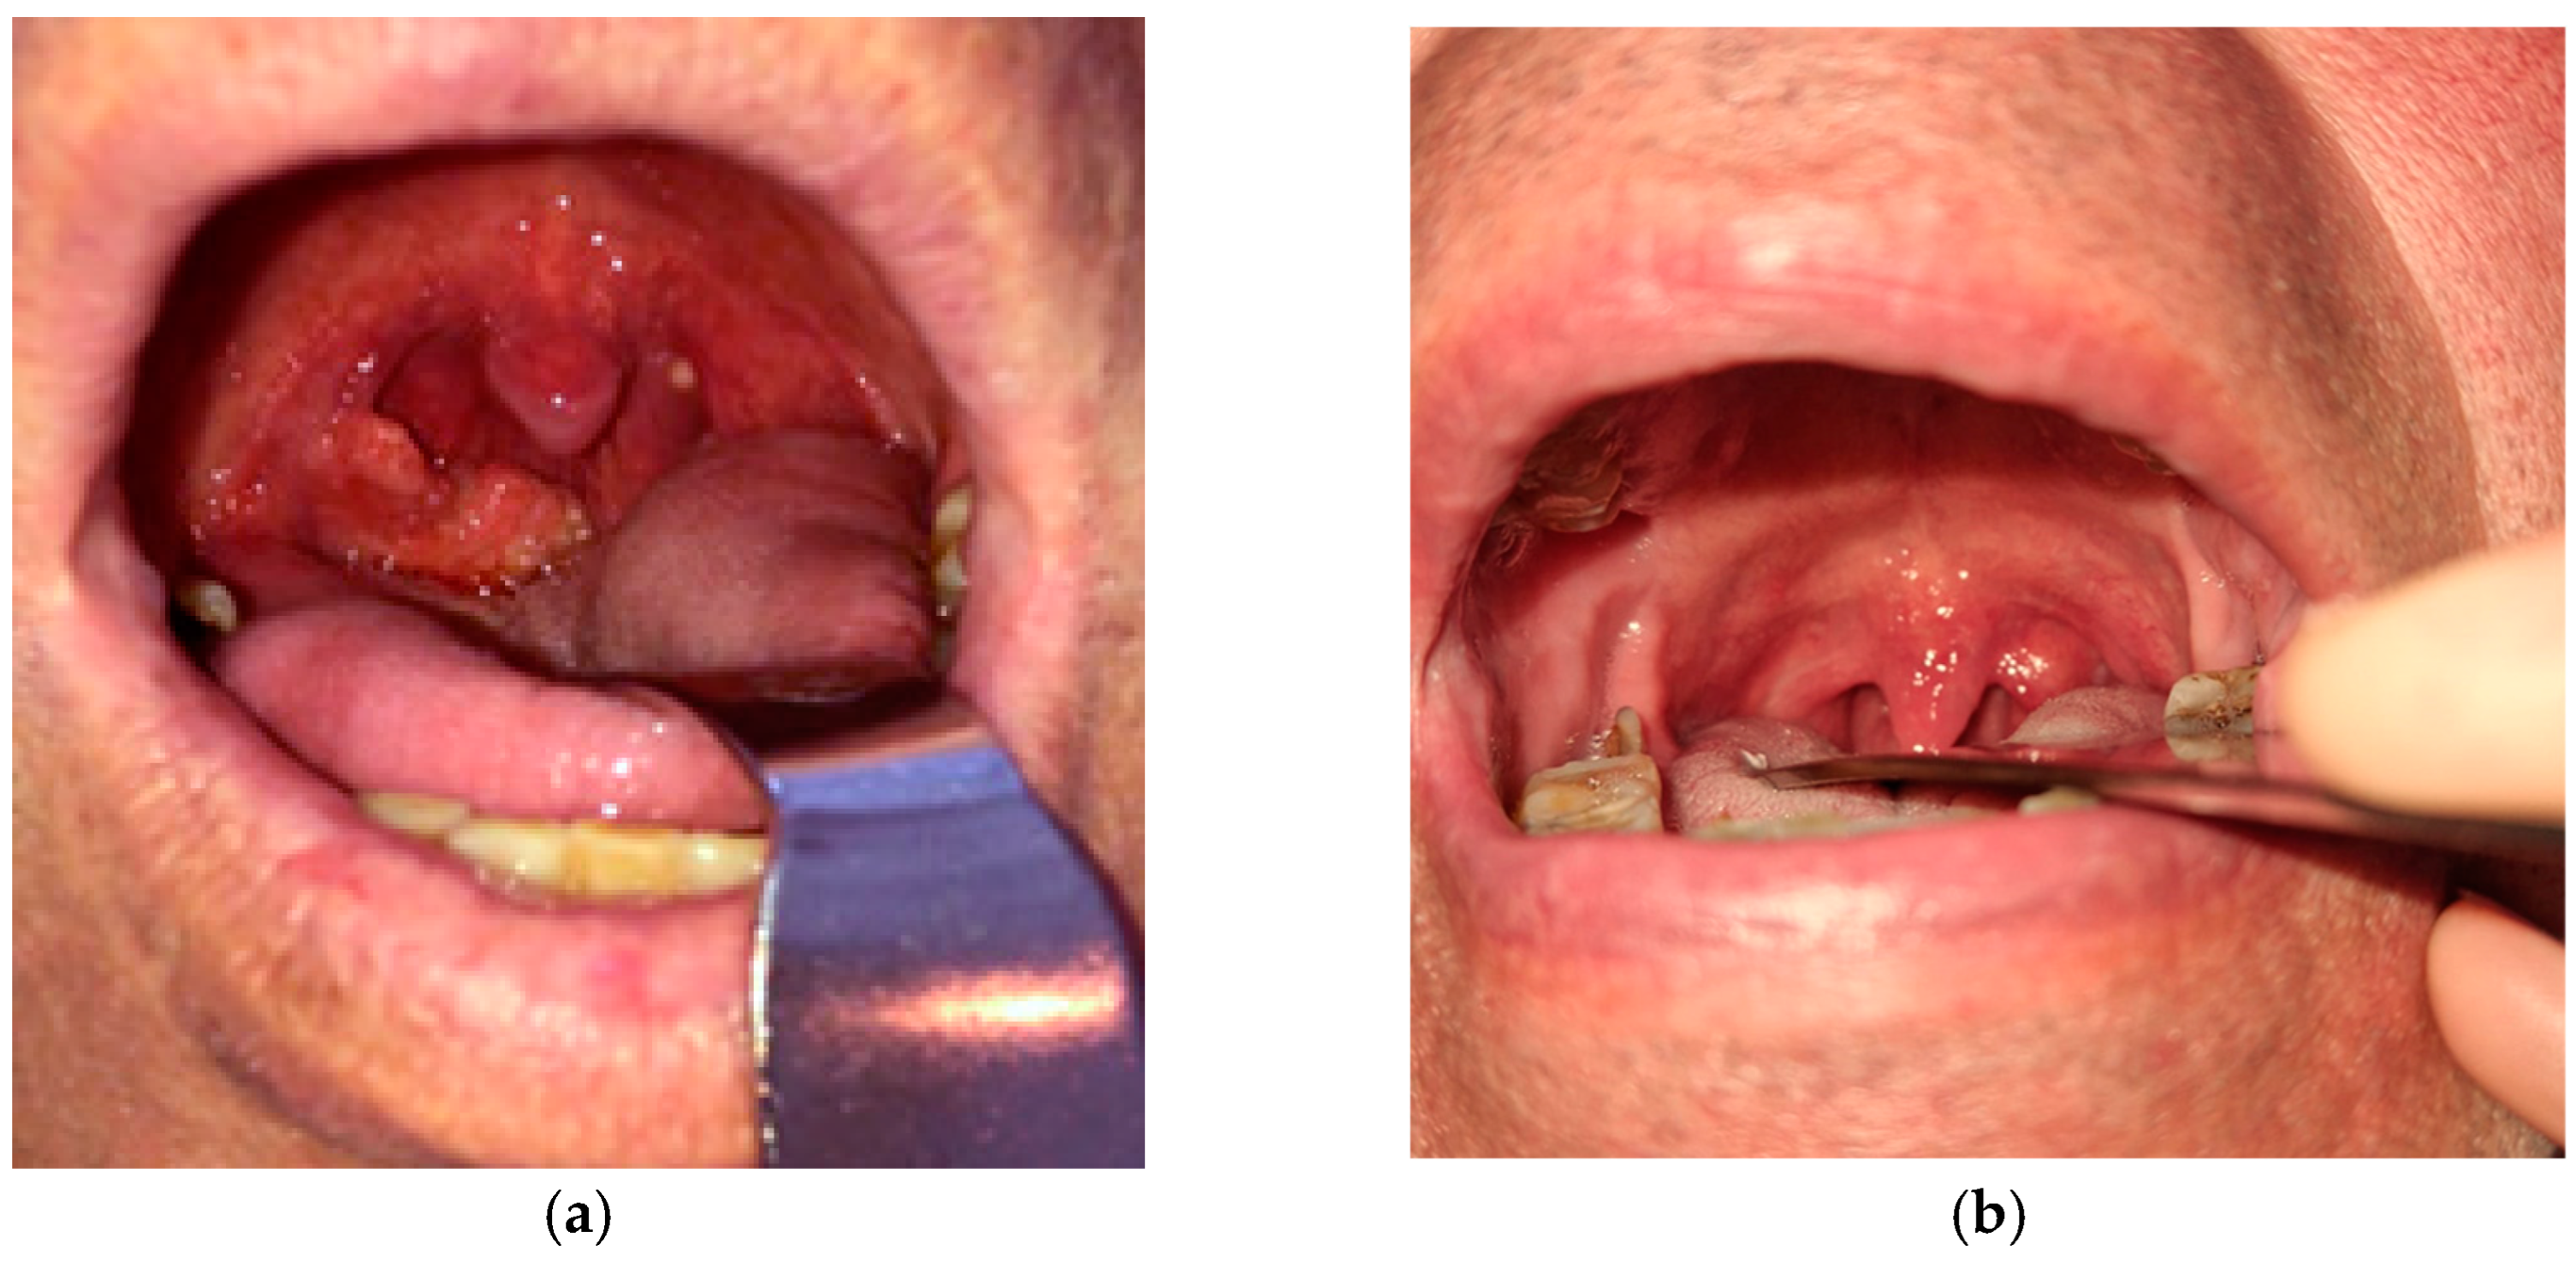

Pharyngeal TB is an exceptionally rare [8,9] and challenging condition to diagnose, often masquerading as other infectious diseases or neoplastic processes. Given its non-specific clinical presentation, differentiating pharyngeal TB from malignancies or other chronic infections requires a high amount of suspicion, especially when the symptoms are ambiguous and the patients do not necessarily come from an endemic region. Our case of pharyngeal TB included the tonsillar region in the oropharynx (Figure 1). We report the case of a 55-year-old male patient with a history of alternating residence between urban and rural environments, potentially transitioning between areas of varying TB incidence. He was a former smoker, having stopped tobacco use 2 years prior to presentation. He had no previous history of pulmonary disease.

Local pharyngeal presentation showed right tonsillar hypertrophy with irregular and ulcerated mucosa. Patchy yellow-whitish deposits on the tonsillar surface were likely representing caseous necrosis or local fibrinous exudate. The adjacent oropharyngeal mucosa appeared erythematous, but without gross swelling or purulence, the main lesion being mostly confined to the tonsillar area.

Figure 1. (a) Clinical presentation of tonsillar TB at diagnosis; (b) Clinical presentation of tonsillar TB after treatment.